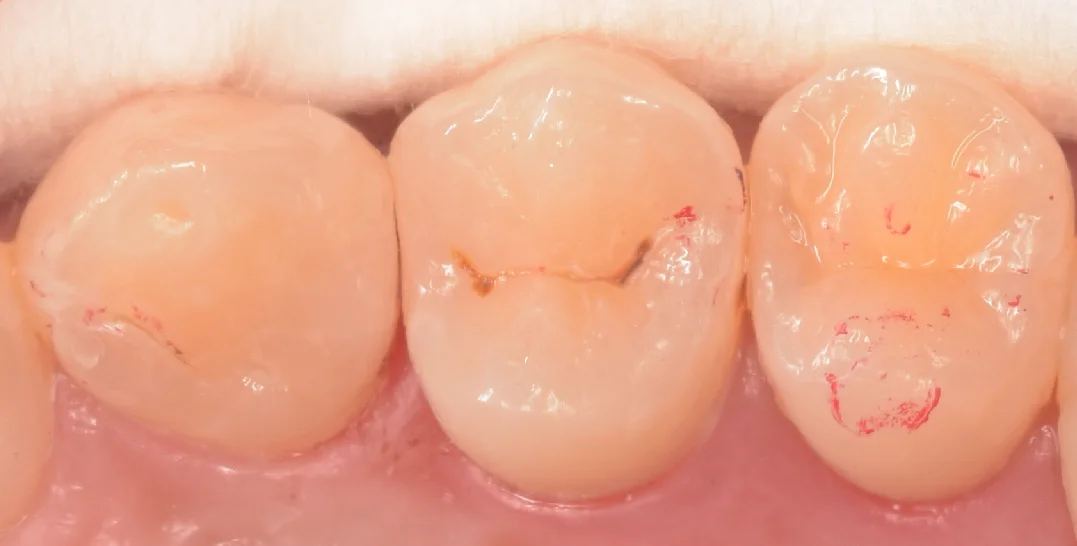

そして治療完了後の写真がこちらになります。

違和感なく綺麗に詰め終われたかと思います。

歯の溝の形態がやや特徴的で、私が良くやるデザインだと違和感が出そうだったため、後ろ半分の部分のデザインを模倣する形で詰めていきました。

歯の形自体もやや難しかったですが、問題なく歯とのあたりも再現できたと思います。

フロスも引っかからず段差もない状態ですので、しっかりと管理していけば長期的に安定して使っていけると思います。